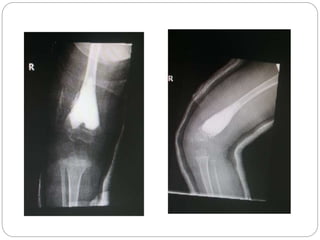

This document discusses 8 oncology cases. Case 1 involves a 40-year old female with right knee pain. Case 2 is a 28-year old male with a left subtrochantric fracture from a MVA who is now experiencing increasing left knee pain and swelling. Biopsy results showed high-grade osteosarcoma. Case 3 is a 30-year old female with breast cancer and bone metastases causing bilateral hip pain.